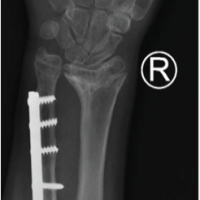

Clinical examination revealed gross swelling over the clavicle, tenderness along the right clavicle, and a restricted range of motion with no neurological deficit. Initially, thought of a lateral end clavicle fracture, stabilization was done by strapping, which aggravated the patient’s symptom and increased prominence over the medial end of the clavicle. Radiographic reassessment showed a medial and lateral end clavicle fracture [Fig. 2].

Figure 2: Pre-operative X-rays showing a bipolar clavicle fracture.